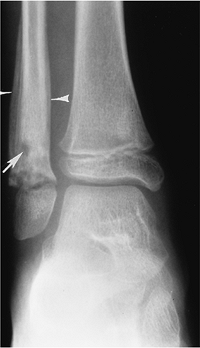

FIGURE 11-2

Anteroposterior (AP) radiograph demonstrating the characteristic appearance of osteomyelitis with a lytic lesion in the metaphysis (arrow) and periosteal reaction along the fibula (arrowheads). |